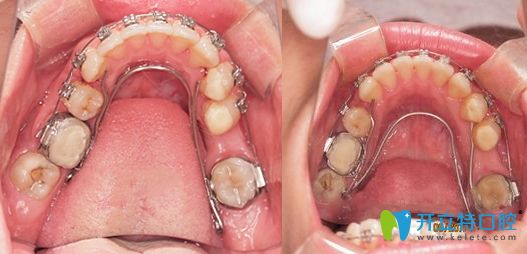

牙弓狹小需要擴弓的病例圖

擴弓矯正的前后效果對比圖